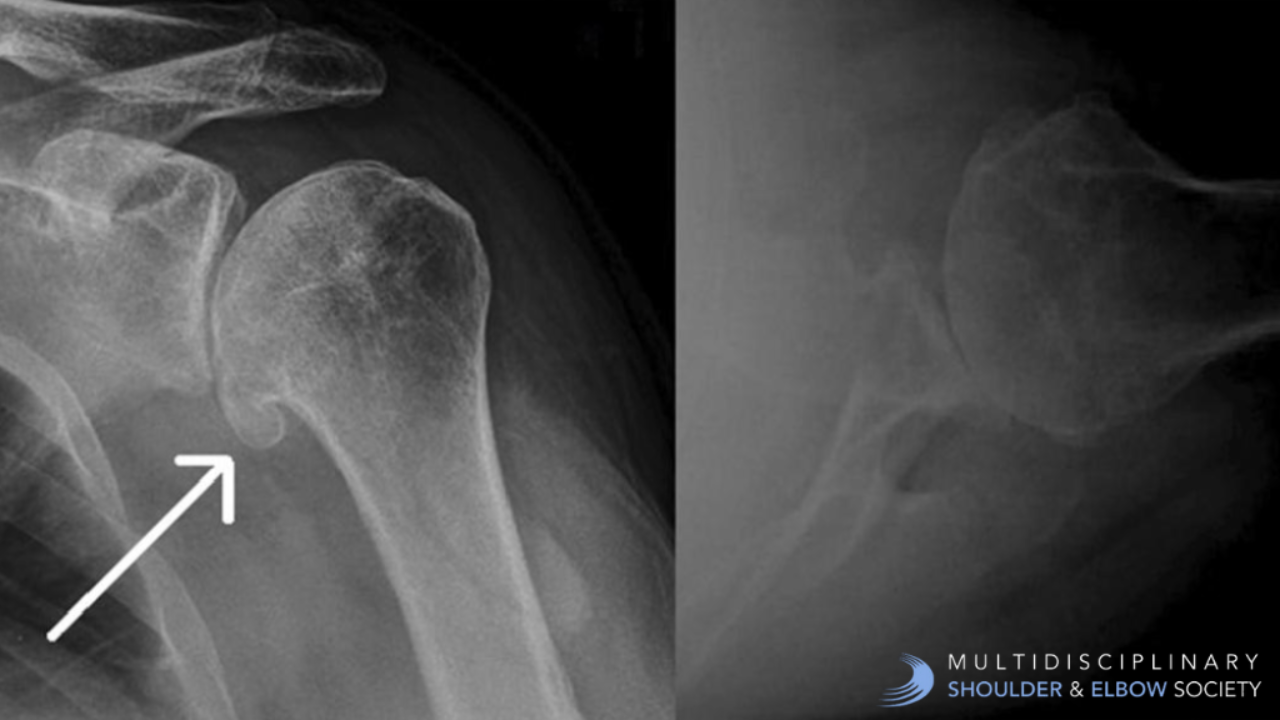

Case of the Week: 71M Shoulder Pain & Limited Mobility case of the week glenohumeral joint glenohumeral joint osteoarthritis osteoarthritis shoulder arthritis shoulder pain

Age/Sex: 71 y/o Male

CC:  Severe right shoulder pain

HPI: 71 y/o, RHD, male presents with severe right shoulder pain. The patient stated that this is a chronic problem that has progressively worsen...